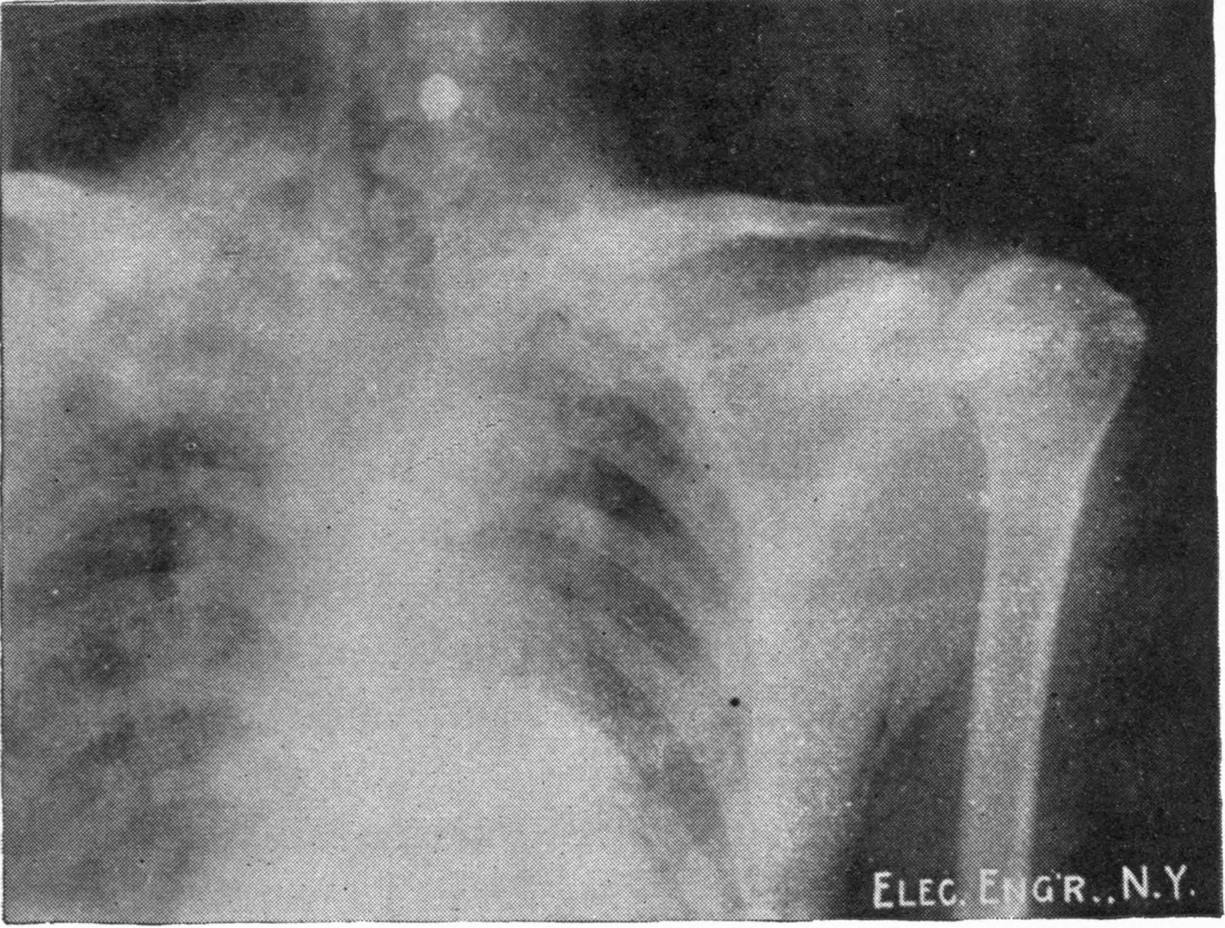

Fig. 3.—Ribs.